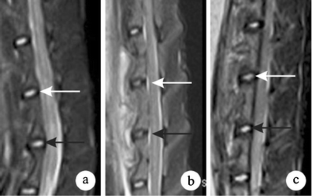

Fig. 1

Fig. 2